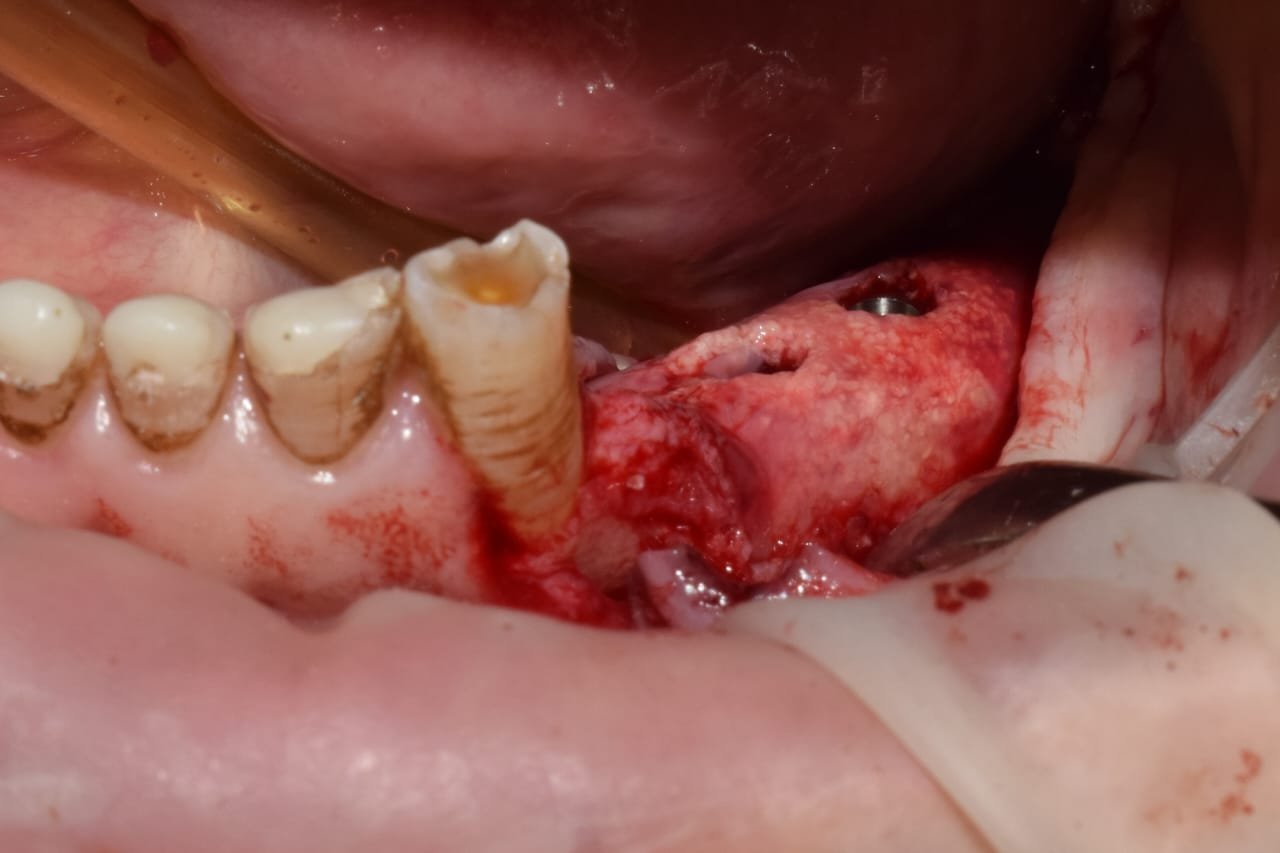

• Colocación de la barrera de zirconio.

• Fijación: secuencia correcta de atornillado.

• Control de estabilidad primaria.

• Diseño de colgajos para ROG vertical.

• Manejo de tejidos blandos.

• Decorticalización y preparación del lecho receptor.